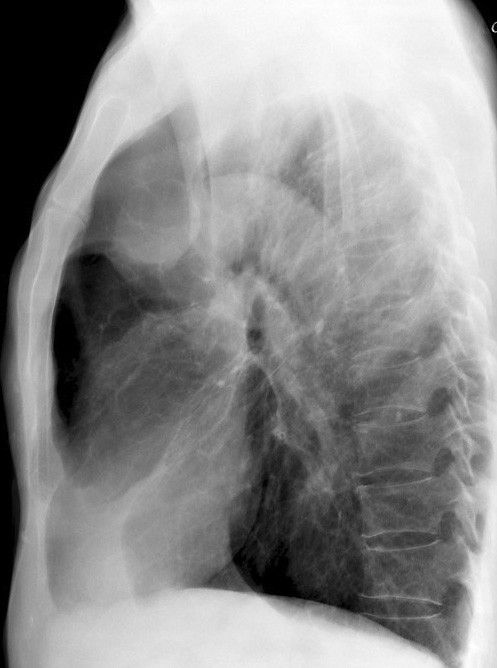

RUL Collapse Case 3 Lateral